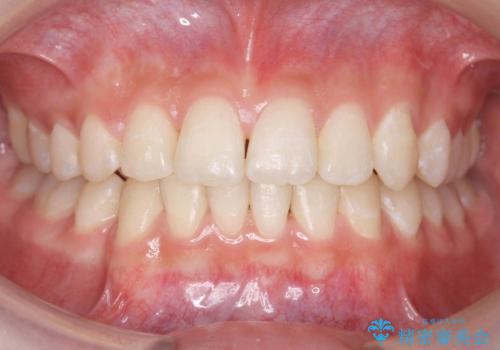

インビザラインで前歯のがたつきを目立たずに矯正治療